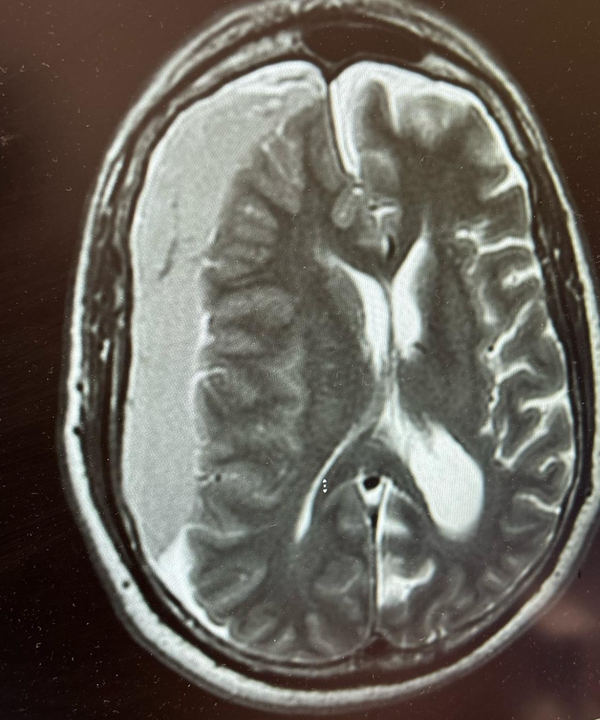

Strokes and Management

What I think you should known regarding the types of strokes and management